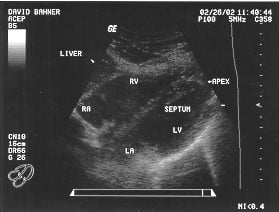

Cardiac - Subxiphoid view (unlabeled)

Cardiac - Subxiphoid view (labeled)